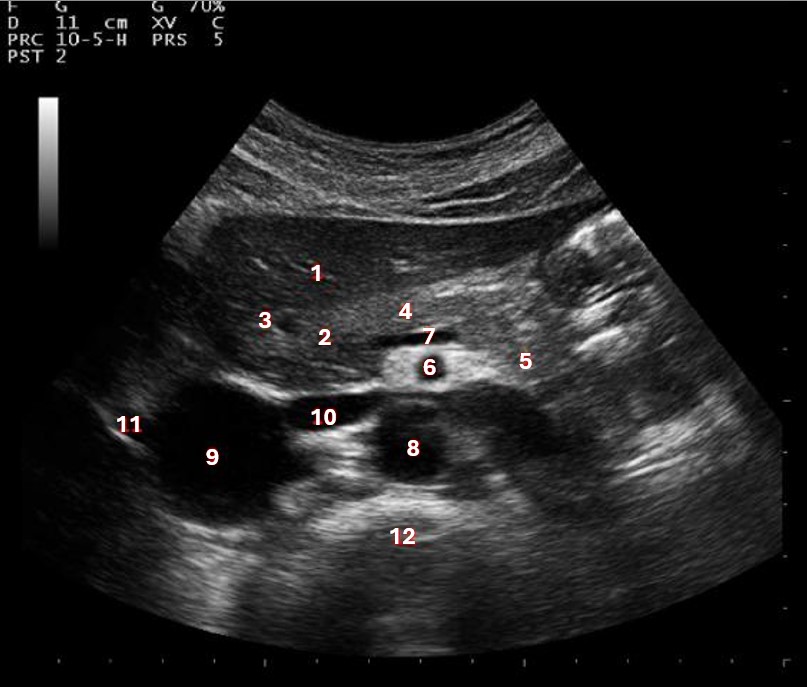

What structure/vessel is indicated by #3?

Gastroduodenal artery

What structure/vessel is indicated by #2?

Head of pancreas

What structure/vessel is indicated by #1?

Medial branch of LPV

What structure/vessel is indicated by #6?

Superior mesenteric artery

Left portal vein

What structures last vessel is indicated by #4?

Medial left lobe

What structures/vessel is indicated by #5?

Tail of the pancreas

What structure/vessel is indicated by #12?

Spine

Which structure/vessel is indicated by #4?

Body of the pancreas

Lateral branch of LPV

What structure/vessel is indicated by #7?

Splenic vein